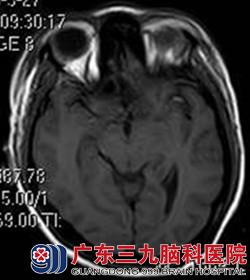

行头颅MR检查提示鞍结节脑膜瘤,大小约4*4cm,完善相关检查后,由鲁明主任主刀,在全麻下行冠状切口右额纵裂入路鞍结节脑膜瘤切除术,术中显微镜下见灰白色肿瘤组织位于鞍上,肿瘤基底部位于鞍结节,质软,双侧视神经、嗅神经被肿瘤压迫明显,大脑前动脉被肿瘤压迫上移,垂体柄位于肿瘤后下方,术中神经、血管均保留完整,肿瘤显微镜下全切,手术顺利结束,术后患者经过专科治疗护理,诉视力、视野明显较术前好转,康复出院。术后病理结果为:脑膜皮细胞型脑膜瘤(WHO I级)。

术前